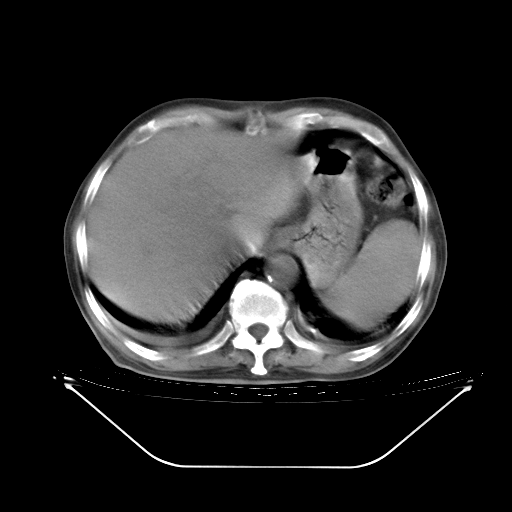

胸腹部CT,诊断意见:左上肺叶钙化灶、左侧胸膜局限性增厚并钙化、胆囊炎。描述部分肺组织呈磨玻璃样改变。

今天复查肺部CT,发现双肺广泛磨玻璃样改变。所以我把3月19日和5月9日相隔50天的肺部CT上传。请大家会诊。

5月9日肺部CT(在4月27日齐鲁医院肺部CT描述部分肺组织磨玻璃样改变,12天后肺组织广泛磨玻璃样改变)